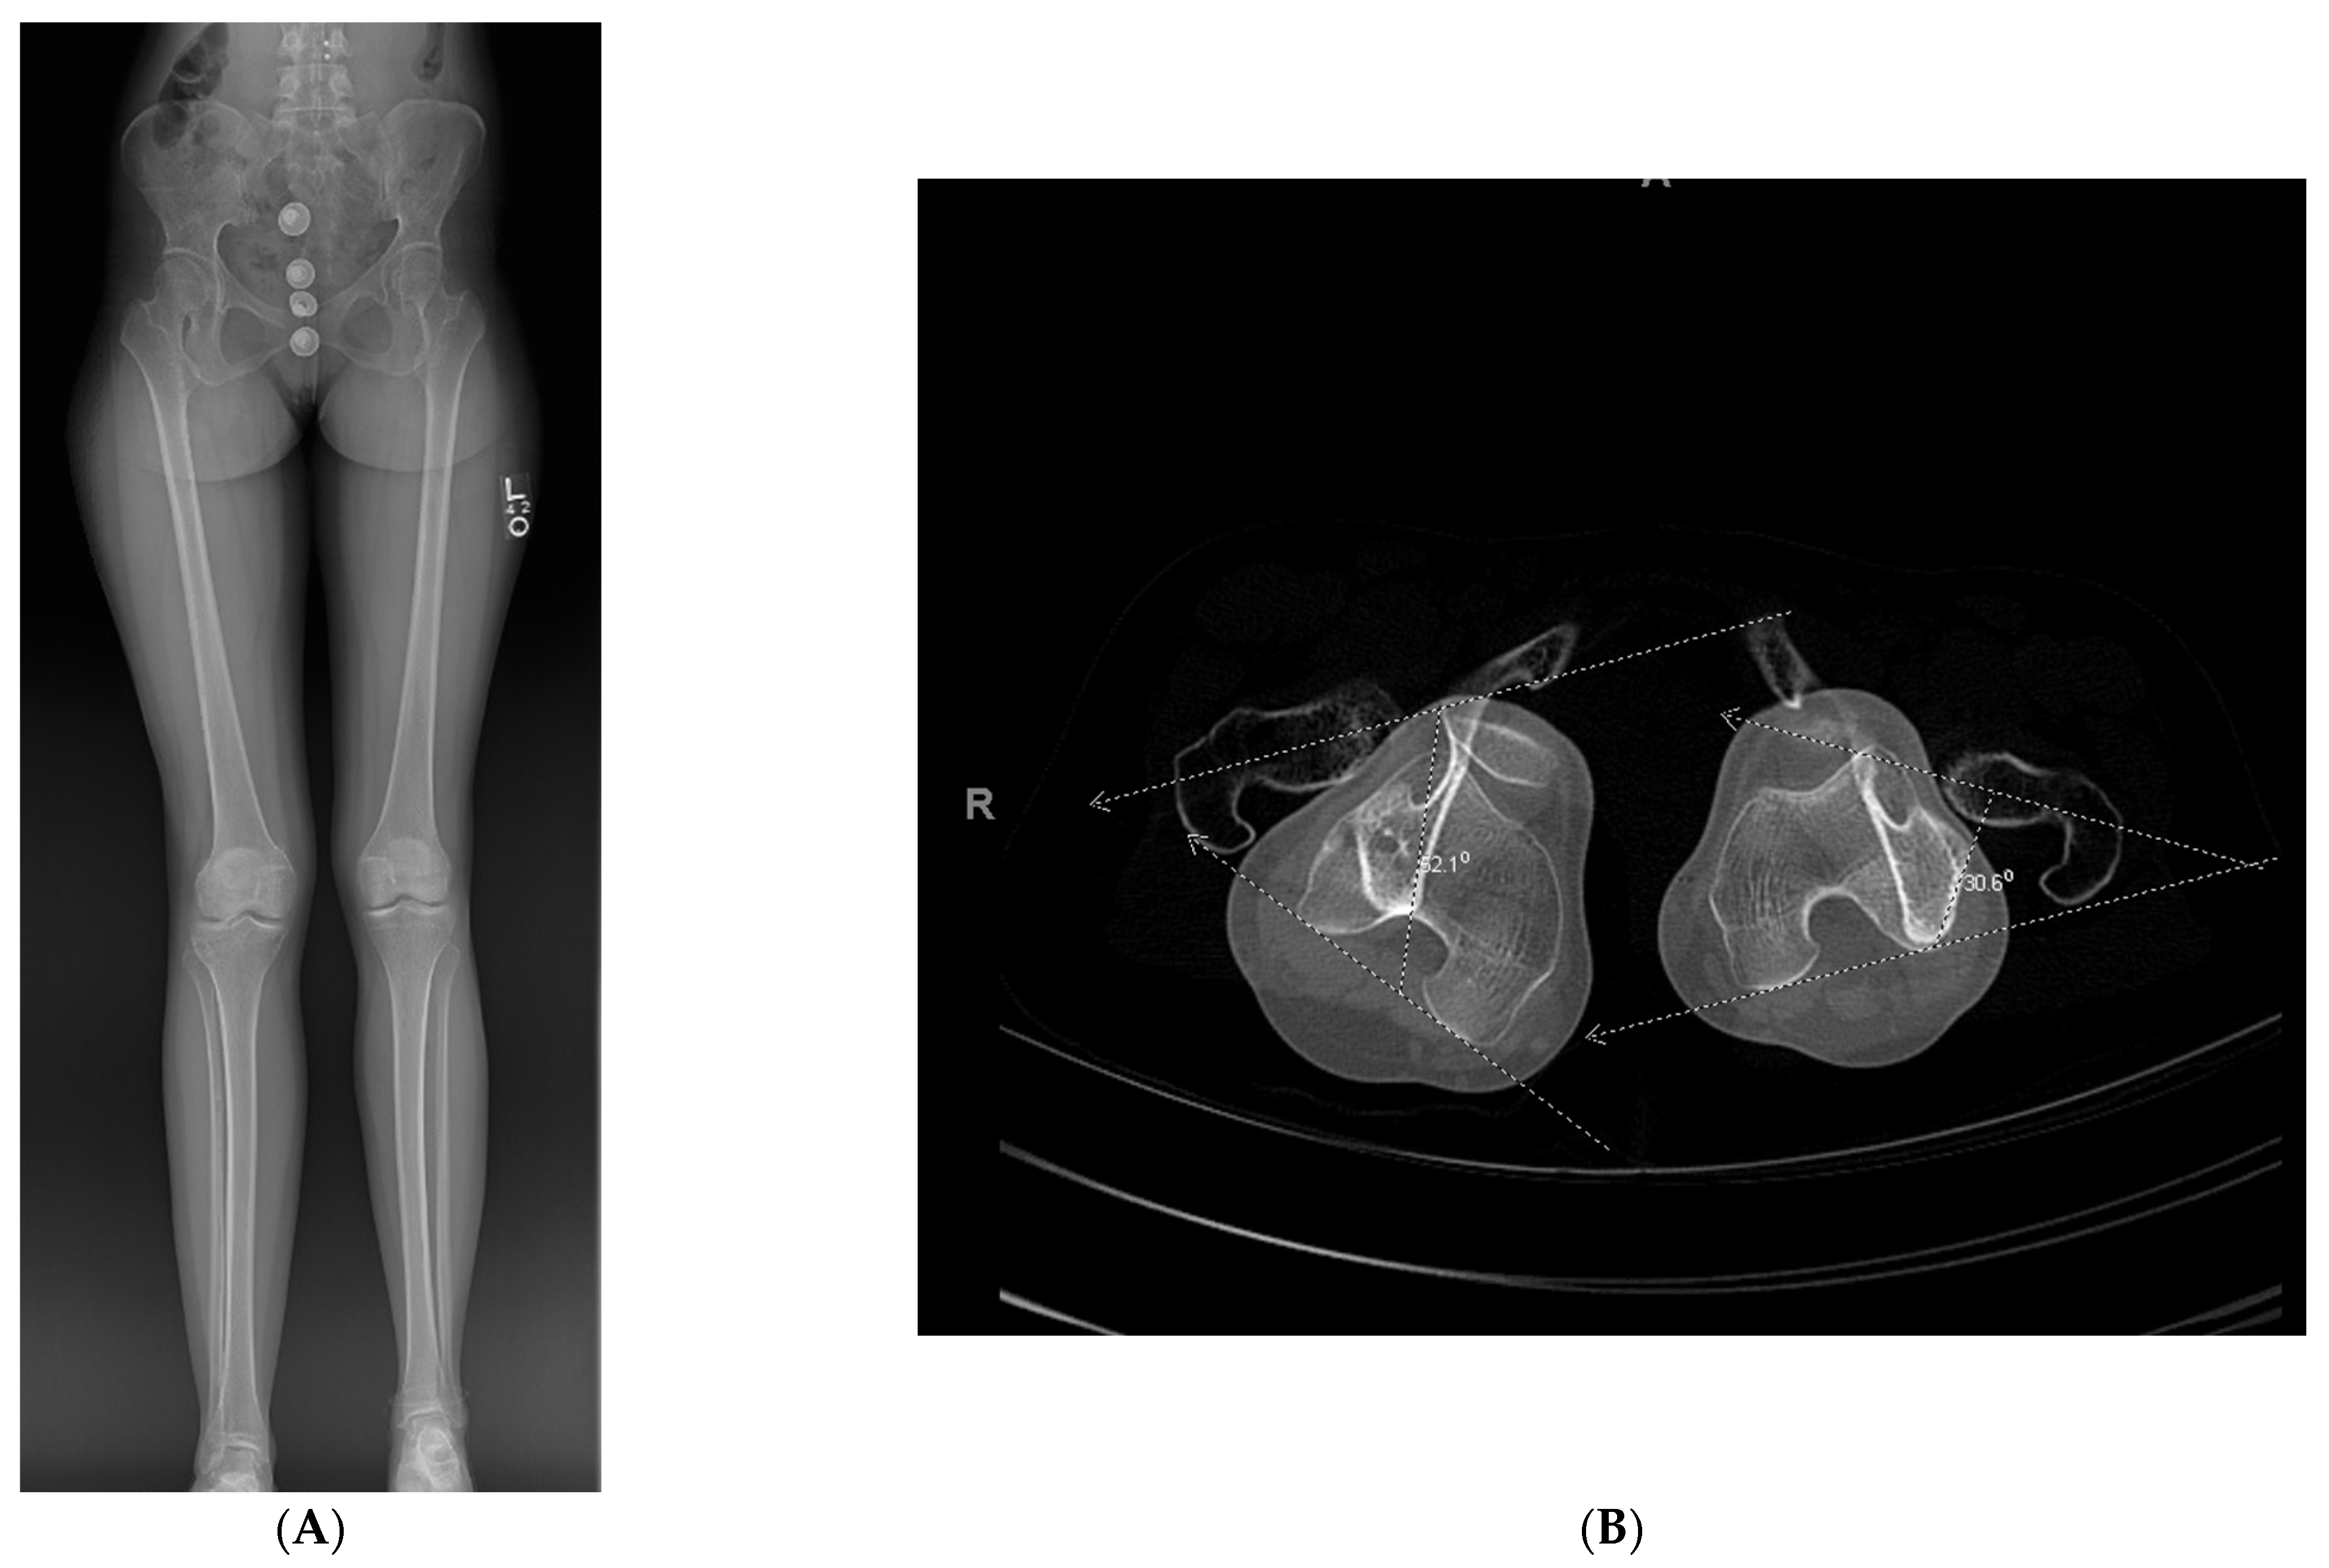

A young adult presented for orthopedic evaluation secondary to a chronic history of right knee pain. Her past medical history was significant for Russell Silver Syndrome. This is a rare genetic disorder characterized with multiple physiologic and phenotypic manifestations including short stature, scoliosis, hand abnormalities, and limb length discrepancy amongst other musculoskeletal issues (references). The physical exam was significant for bilateral genu valgum more pronounced on the right lower extremity, a limb length discrepancy with a longer right lower extremity, and excessive femoral anteversion with significant variance in hip range of motion. A full-length radiographs (Figure 5A) and computed tomography (CT) anteversion study (Figure 5B) demonstrated mild lateral mechanical axis deviation (MAD), a 2 cm LLD and 52° of femoral anteversion of the right lower extremity. Her lateral MAD was thought to be related to rotational malalignment than valgus malalignment. Magnetic resonance imaging (MRI) of the right knee ruled out any intra-articular pathology as a source of morbidity. A trial of physical therapy and non-steroidal anti-inflammatory drugs did not resolve her knee pain. She opted for surgical intervention (Figure 5C–H) to ameliorate the patellofemoral pain and LLD. Her pain subsided significantly after surgery. She went on to heal her osteotomy uneventfully.

Figure 5. (A): Full length standing radiograph. There is not a diaphyseal malunion; the patient has a 2 cm LLD, and rotational malalignment. The clamshell osteotomy was used to shorten and correct the rotational malalignment. (B): Computed tomography anteversion study demonstrating a 52° degree femoral anteversion and 30° femoral anteversion of the right and left lower extremity, respectively. (C): Intraoperative fluoro view showing bicortical drill holes being created in a diaphyseal segment measuring 2 cm. (D): An osteotome is used after the bicortical drill holes. Subsequently, a saw was used for the perpendicular cuts at the proximal and distal aspect of the osteotomy to create the clamshell. (E): Lateral fluoro view illustrating the clamshell osteotomy. No secondary fracture lines were propagated during this osteotomy. (F): 2.0 kirschner wire was placed in the proximal and distal aspect to be used as reference points when correcting the rotational malalignment. (G): AP fluoroscopic view after the clamshell segment was mobilized, and rotational malalignment was corrected. Her right knee was taken through range of motion after surgery to ensure there was not any patellofemoral maltracking. (H): AP and lateral femur XR demonstrating osseous healing of osteotomy at 6 months follow up.